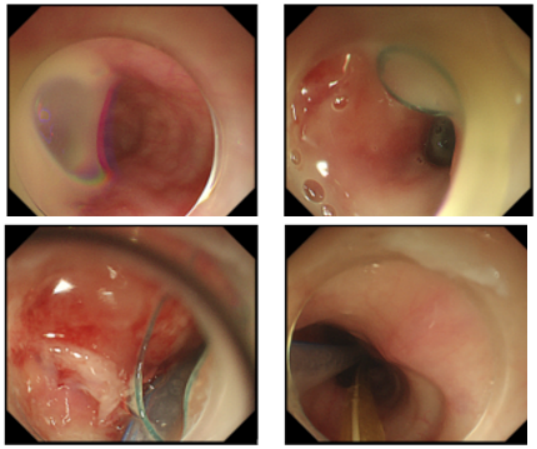

2024年8月29日,患者呼吸困难再次加重。胸部CT示:食管和右侧胸腔连通(图5)。急诊胃镜示:距门齿31 cm可见一食管瘘口(0.7 cm),窦腔,可见较多脓性分泌物及胸腔引流管,于瘘口处置入引流管(图6)

图片

5  胸部CT(2024-08-29)

6  急诊胃镜检查